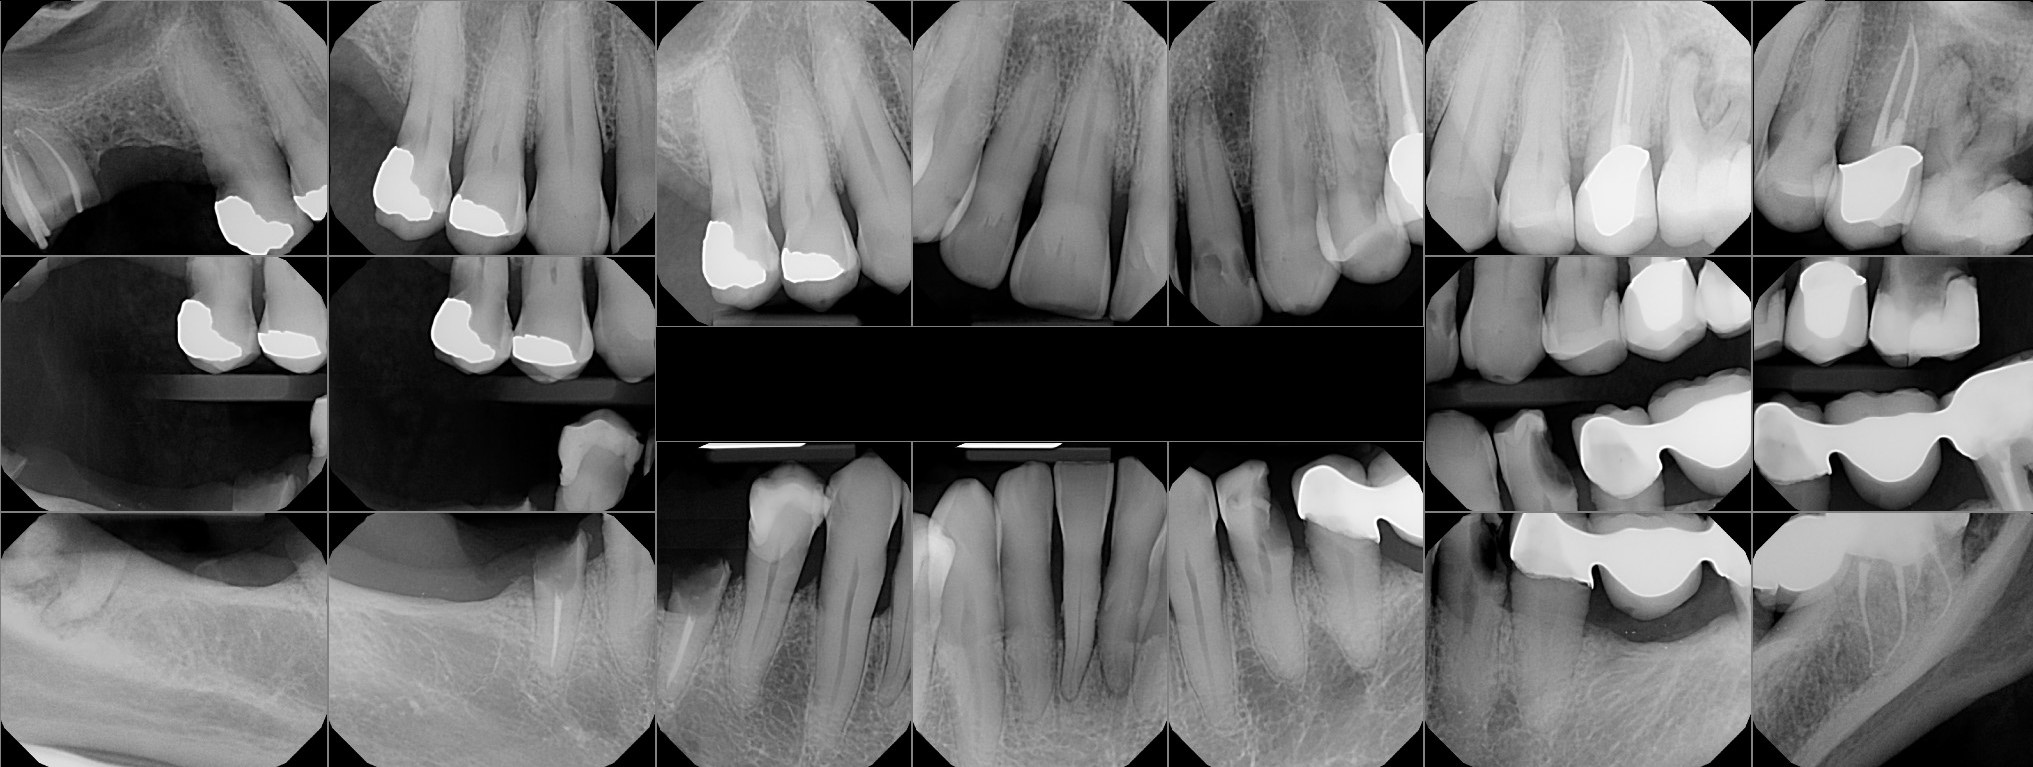

Dental Auction No. 10074: All on 6- upper and lower arches

Auction images